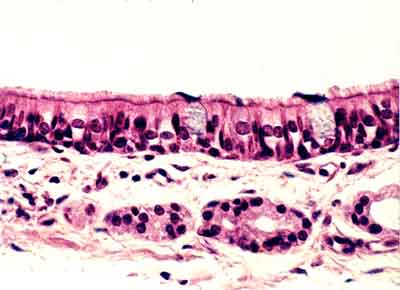

| HG-02 Mucosa nasal (Hematoxilina-eosina) |

Visión general: fragmentos de cornete

nasal que permite observar en superficie un revestimiento epitelial con

aspecto de pluriestratificación, que asentando sobre un conjuntivo

con vasos y glándulas se denomina mucosa respiratoria y se mantiene

por un eje esqueletógeno en la porción media.

Visión específica: al observar

el epitelio constatamos, a mayores aumentos, que la densidad celular y

por tanto nuclear varía en número y disposición.

En algunos campos aparecen con aspecto alargado los citoplasmas y los

núcleos en un único estrato, mientras que la forma mas habitual

de disposición es adoptando el patrón de pseudoestratificación.

Las células de reserva, triangulares y pequeñas, en los

niveles mas basales del epitelio presentan un núcleo redondeado,

las verdaderamente cilíndricas, mucho mas numerosas se encuentran

densamente dispuestas con lo que sus núcleos ovoides pueden situarse

tanto en los niveles intermedios como ocupando el citoplasma mas apical,

si bien el ultimo tercio del mismo no presenta núcleos sino las

diferenciaciones celulares que son en este tipo de epitelio dobles: las

células mas eosinófilas presentan un denso ribete de cilios

y las mas pálidas, con esta técnica, contienen secreción

de tipo mucoso.